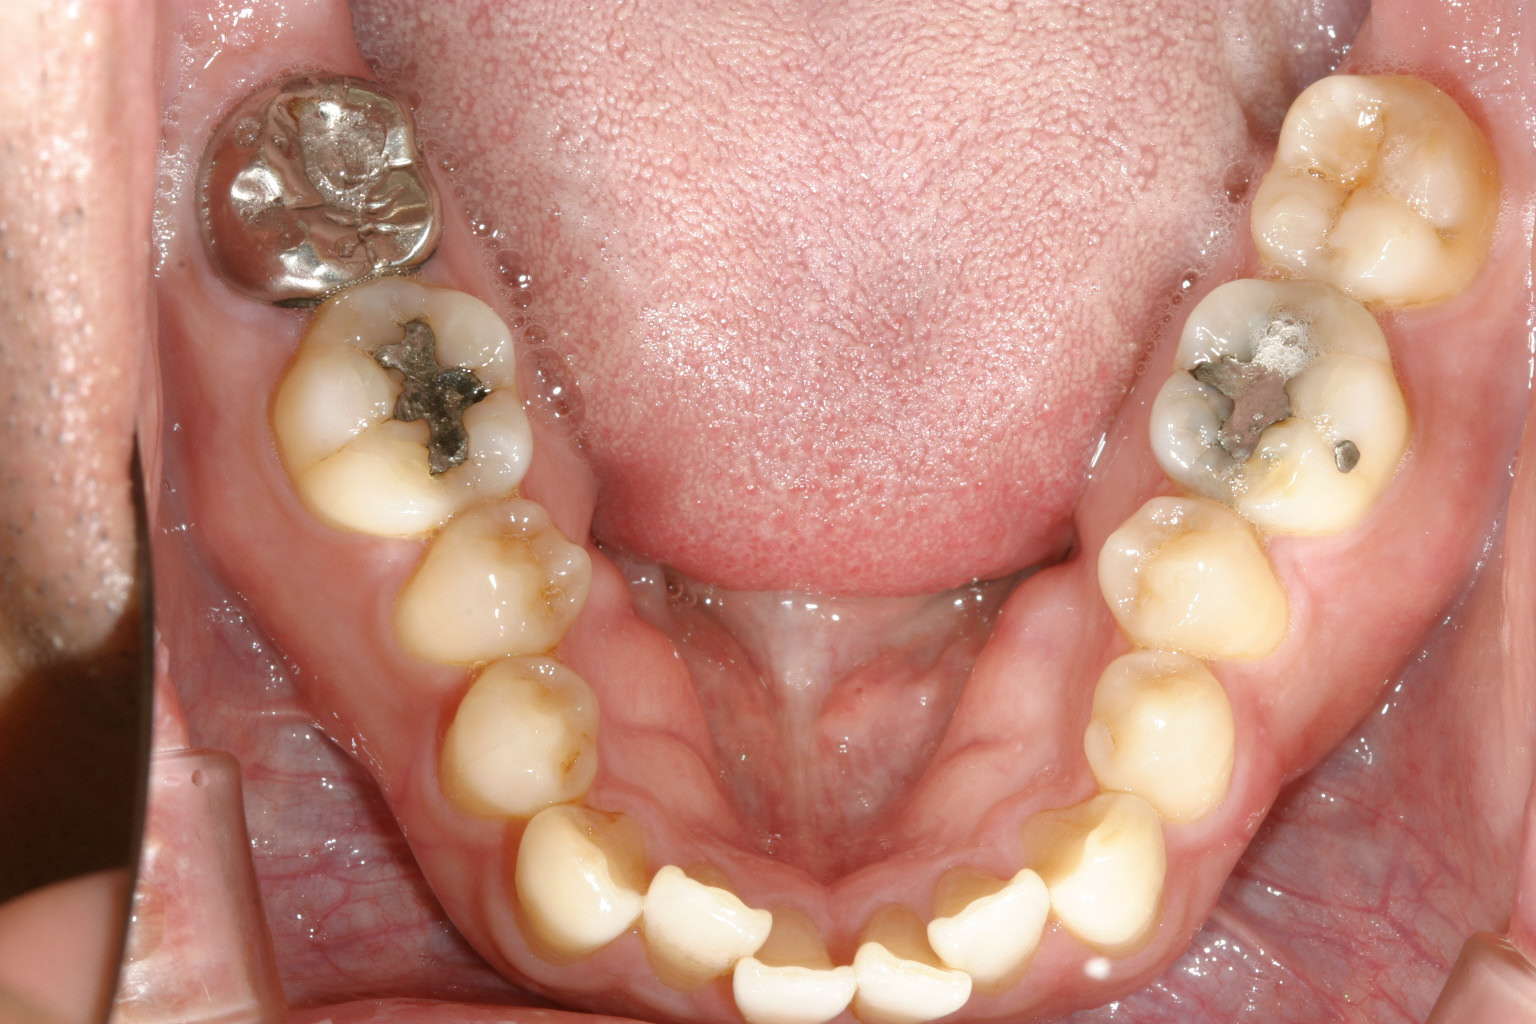

下顎もアーチが狭く叢生がきついです。